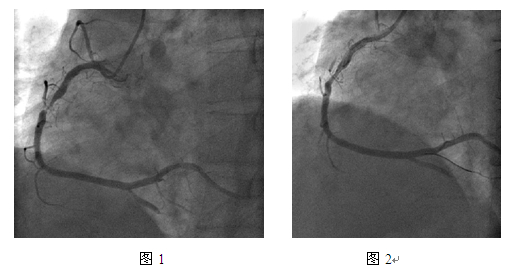

冠脉造影:右冠支架内再狭窄90%(图1)。

JR4.0指引导管,BMW导丝,预扩张球囊Fire Star 2.5mm x 15mm,最大20atm扩张;双导丝球囊Score Flex 3.5mm x 15mm,最大16atm扩张(图2);后扩张球囊Sapphire NC 3.75mm x 15mm,最大10atm;紫杉醇药物洗脱球囊(PEB)Sequent please 3.5mm x 20mm,最大18atm扩张,持续60s(图 3)。最终效果满意(图 4)。